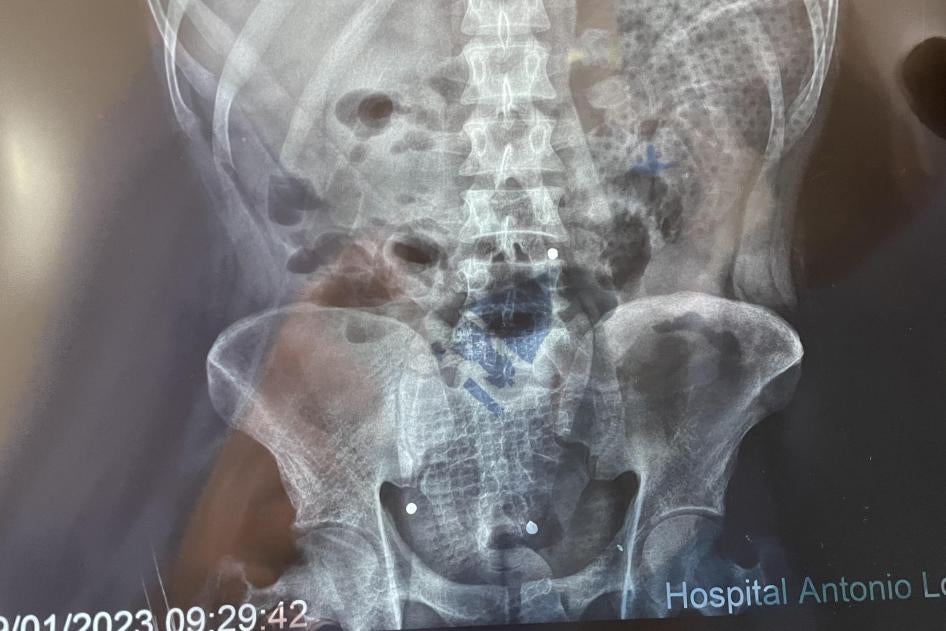

Revisamos autopsias e informes de balística, registros médicos y otros documentos, y consultamos con expertos forenses. Visitamos el Hospital Antonio Lorena en Cusco y el Hospital de la Policía Nacional del Perú en Lima.